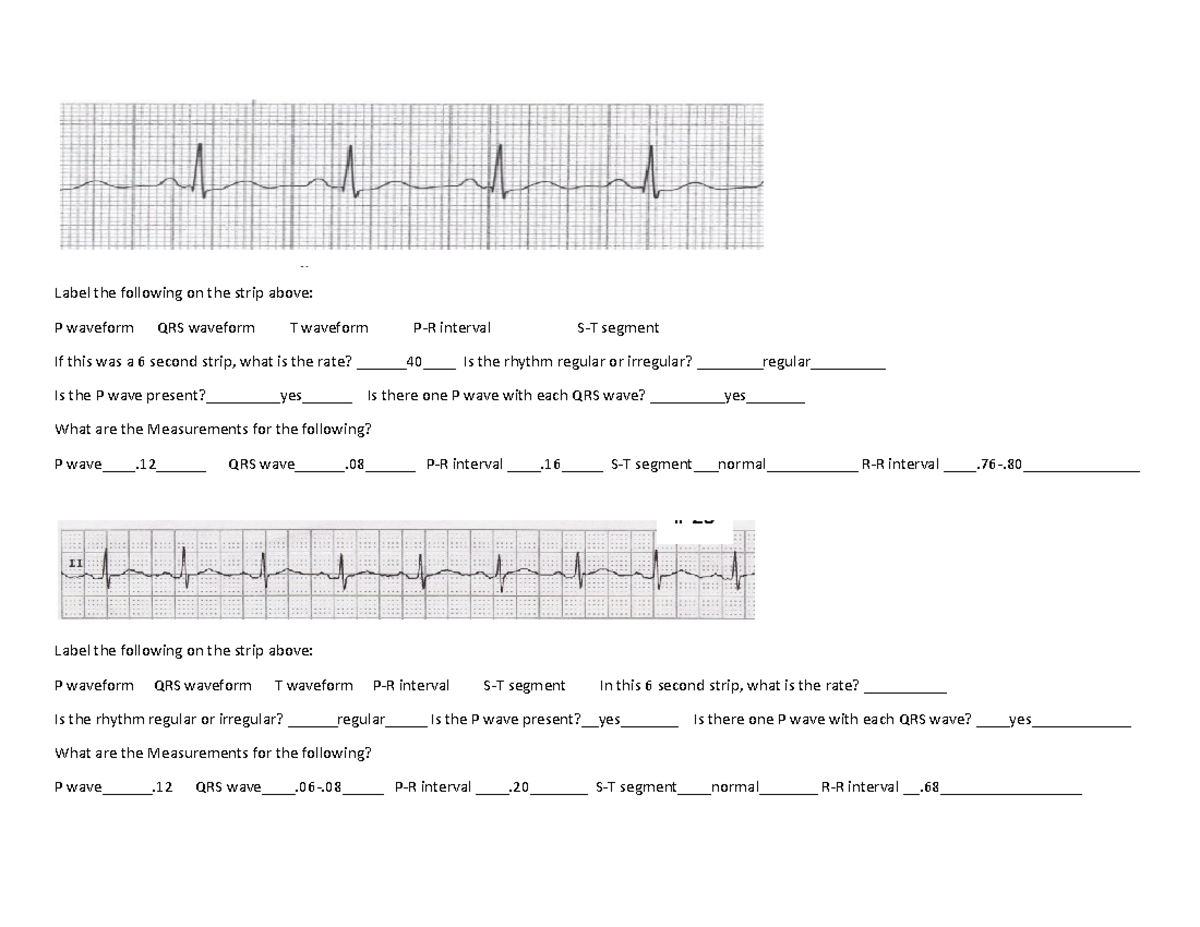

CBC perfusion ecg practice answers Label the following on the strip